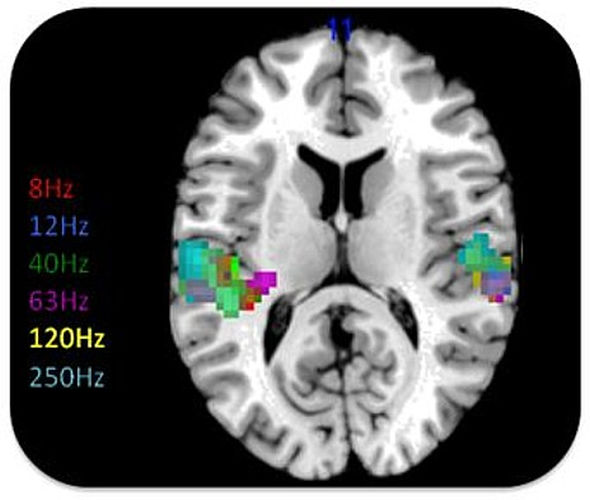

Aunque el oído humano no percibe sonidos por debajo de 20 Hz, el cerebro todavía encuentra una manera de interactuar con los infrasonidos, como se puede ver con el uso de tomografía axial computarizada.

Persinger señala claramente que cuando uno trata de estimular las experiencias fuera del cuerpo, el cerebro comienza a emitir frecuencias particulares en el hemisferio derecho entre 4 y 7 Hz, precisamente en la región espectral que, de nuestros cálculos, corresponde a las frecuencias de la tríada A, M y S (Alma, Mente y Espíritu).